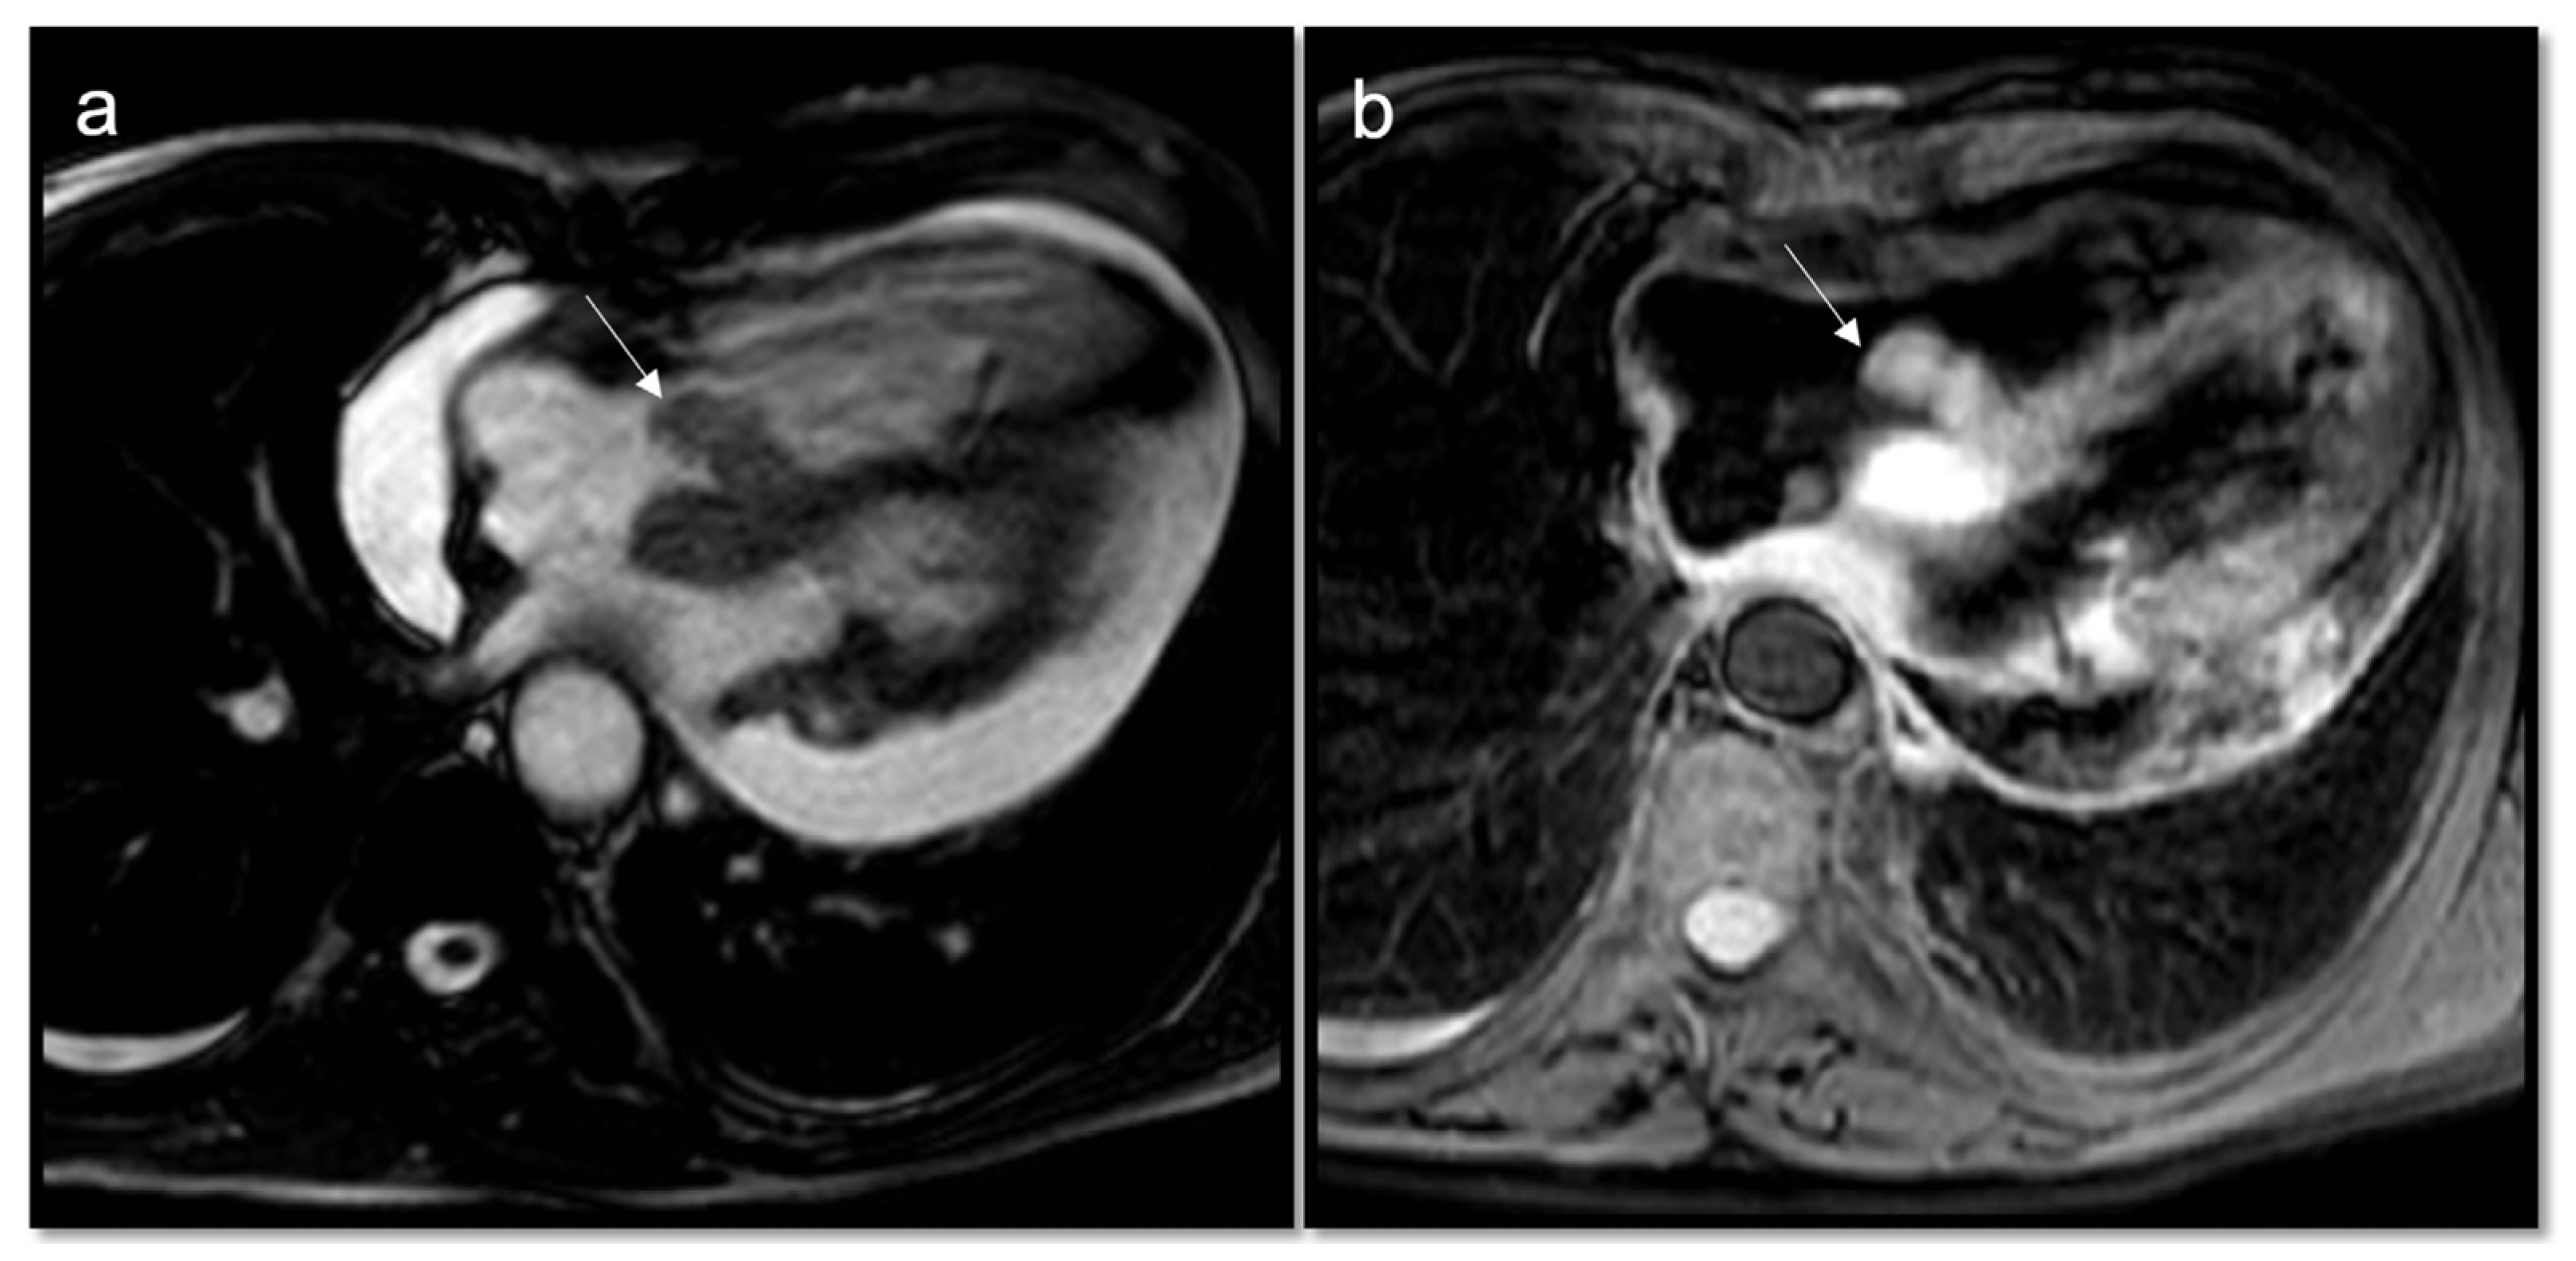

Figure 2.

A 78-year-old man arrived at the emergency department with a two-week history of progressively worsening dyspnea, cough, and weight loss. CMR cine sequences show a conspicuous pericardial effusion (a) and an ill-defined infiltrative mass (arrow) at the level of the tricuspid valve, hyperintense on T2w Fat Sat (b). Biopsy confirmed it as a primary cardiac lymphoma, a very rare entity.